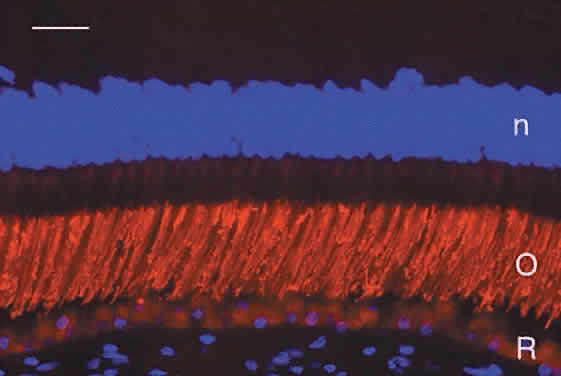

Humans have a single type of rod with a long, thin outer segment containing the visual pigment, rhodopsin, which absorbs maximally at 500 nm. The cone outer segments are shorter and wider and somewhat conical. Each of the three cone types contains a different cone opsin that absorbs maximally in the red (564 nm; L cones), green (533 nm; M cones), or blue (437 nm; S cones) region of the spectrum. The visual pigments can be demonstrated by immunocytochemistry using antibodies specific for the different proteins. Rod outer segments are strongly labeled with anti-rhodopsin (Fig. 6). The composition of the red cone pigment is so similar to that of the green cone pigment that they cannot be differentiated by immunocytochemistry, but the majority of cone outer segments are labeled with an antibody that recognizes both red- and green-sensitive cones (Fig. 7A). A minority of the cones are blue-sensitive (see Fig. 7B).

Fig. 6. Immunocytochemical demonstration of rhodopsin (red) in human rod outer segments (O). R, retinal pigment epithelium. Cell nuclei (n) are counterstained blue with DAPI. Bar = 20 μm.